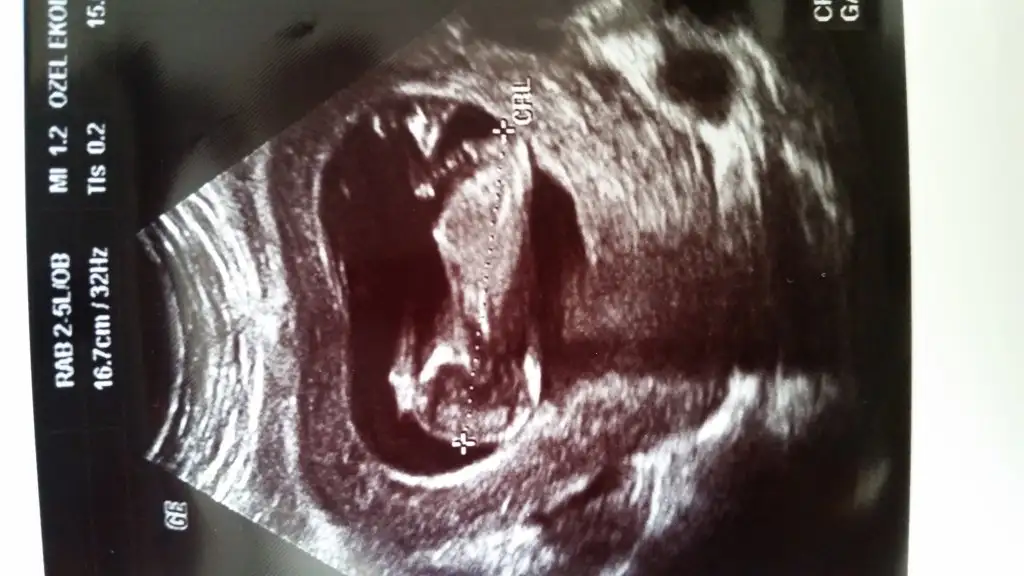

dr soylemeden siz gorun genital nub teorisi ( bebegin cinsiyeti)

Kızlar bana da yorum yapabilirmisiniz belli oluyor mu bilmiyorum ama açıkçası ben pek anlamıyor bebisim fotoda 12+4 haftalık tüp bebekle oldu sizce cinsiyeti nedir doktor ancak 16. Haftada söyleyebilirim dedi 12 haziranda bir daha ki kontrolüm çok merak ediyorum lütfen yardımcı olun

Kızlar bana da yorum yapabilirmisiniz belli oluyor mu bilmiyorum ama açıkçası ben pek anlamıyor bebisim fotoda 12+4 haftalık tüp bebekle oldu sizce cinsiyeti nedir doktor ancak 16. Haftada söyleyebilirim dedi 12 haziranda bir daha ki kontrolüm çok merak ediyorum lütfen yardımcı olunEki Görüntüle 1528009

bebeginiz erkek saglikla dogsun ins...

Bariz belli erkek diyorum ben...belli olunca lutfen yazarsaniz